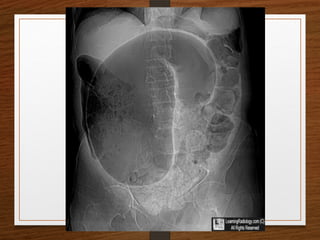

Sigmoid volvulus

The inverted U-shaped loop is usually massively distended

Commonly devoid of haustra, an important diagnostic point.

The ahaustral margin can often be identified overlapping respectively

 the lower border of the liver shadow (the liver overlap sign),

 the haustrated, dilated descending colon (the left flank overlap sign)

 the left side of the pelvis (the pelvic overlap sign).

The top of the sigmoid volvulus usually lies very high in the abdomen

(above the level of T10) with its apex on the left side.

Signs

 Grossly distended loop of sigmoid colon

 Coffee bean sign

 Air – fluid ratio > 2:1

 Lack of haustra

 Apex above 10th

thoracic vertebra

 Liver overlap sign

 Left flank overlap sign

 Pelvis overlap sign

 Bird of prey /twisted bird beak appearance

Sigmoid volvulus The invertedU-shaped loop is usually massively distended Commonly devoid of haustra, an important diagnostic point. The ahaustral margin can often be identified overlapping respectively  the lower border of the liver shadow (the liver overlap sign),  the haustrated, dilated descending colon (the left flank overlap sign)  the left side of the pelvis (the pelvic overlap sign). The top of the sigmoid volvulus usually lies very high in the abdomen (above the level of T10) with its apex on the left side.

• 31.

Signs  Grossly distendedloop of sigmoid colon  Coffee bean sign  Air – fluid ratio > 2:1  Lack of haustra  Apex above 10th thoracic vertebra  Liver overlap sign  Left flank overlap sign  Pelvis overlap sign  Bird of prey /twisted bird beak appearance